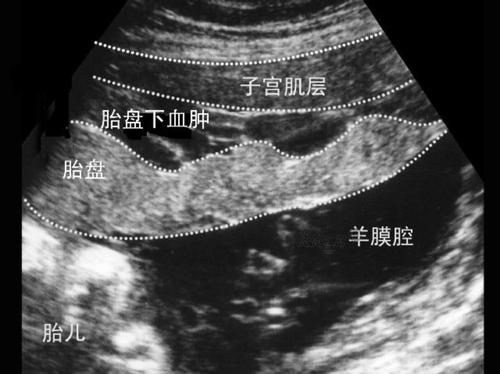

急诊产科医生看到宝妈的时候,宝妈有明显的烦躁不安,而且腹痛明显,简单的做了一下查体:宫高36cm(可是之前一周只有32cm),腹围106cm,腹部有明显的压痛,并成持续性。最让人揪心的是产科医生就是找不到胎心,产科医生越找越担心,而宝妈也害怕起来。结果床边的B超提示没有胎心,前壁胎盘的后面全是絮状物。考虑胎盘早剥。当听到胎心没有的时候,宝妈真的控制不住的哭了。可是哭也没用,面对宝妈的是剖宫产。很多人会质疑,既然宝宝都不好了,为什么还要剖宫产,因为胎盘早剥,如果处理不及时,宝妈的命也就危险了,胎盘早剥,死胎,会导致凝血功能异常。后面通过剖宫产,宝妈是平安的。

作为产科医生可以明确得告知你是B超,如果有磁共振那就更好了。但是B超不支持,而临床症状像胎盘早剥,也应该考虑胎盘早剥。